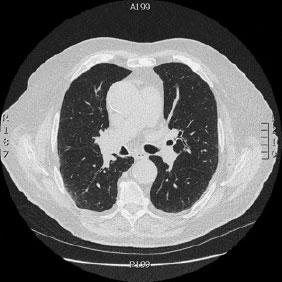

Tomografía computarizada Tórax

< Volver a "Tomografía Computarizada (TC) con Inteligencia artificial"Se utiliza para el estudio de los pulmones y diferentes estructuras del tórax (mediastino, ganglios, costillas,…)